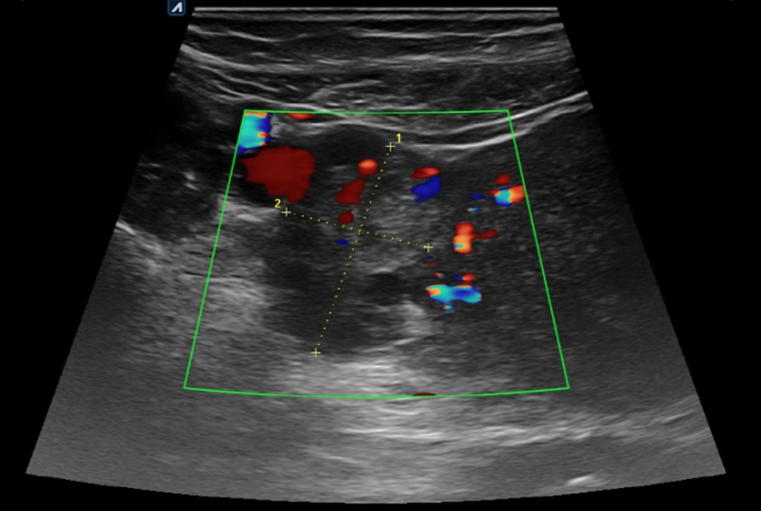

생리통으로 오인하여 내원한 복통 환자의 초음파.

하복부의 장관 부종이 확인됩니다.

골반에 복수 의심 소견이 관찰됩니다.

*난소종양 의심 소견 확인되어 대학병원 의뢰되었습니다.